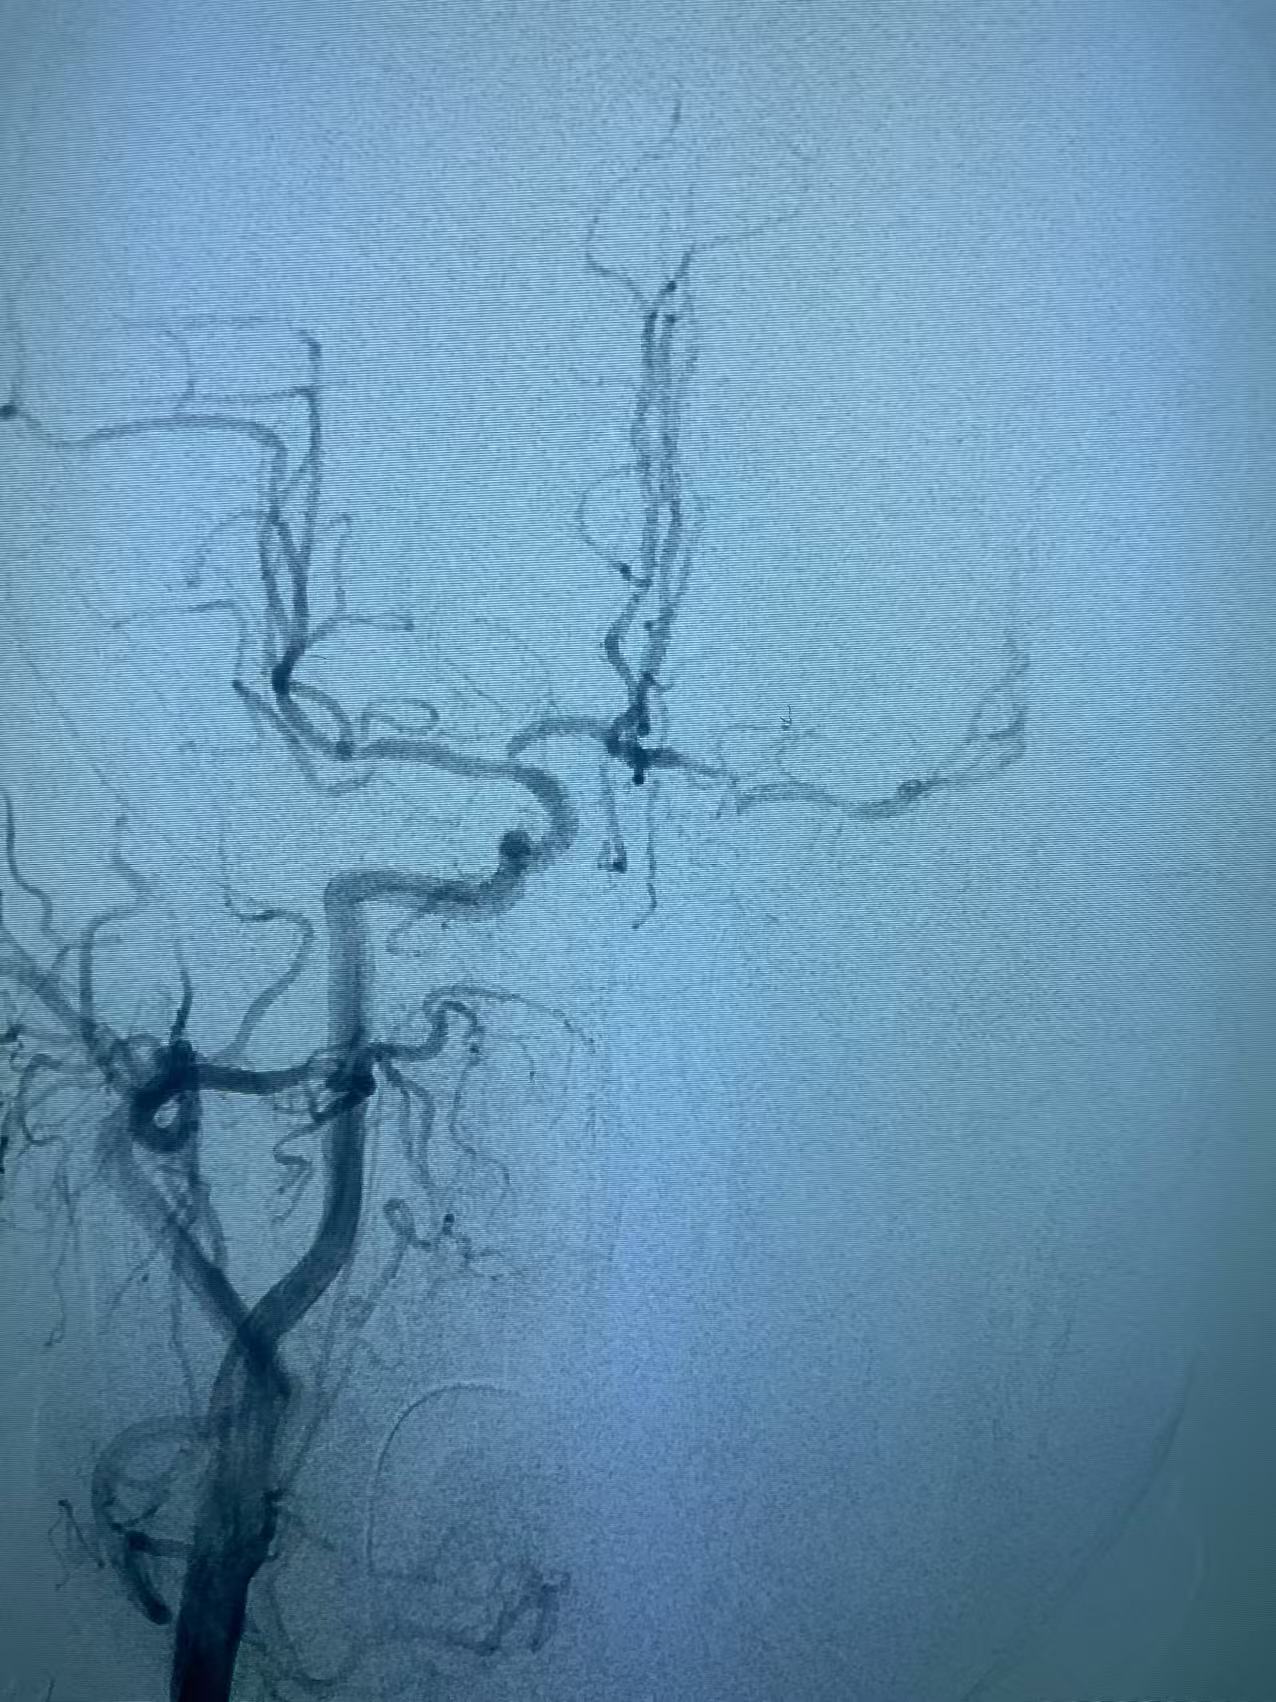

颈内动脉开口重度狭窄基础之上的急性闭塞